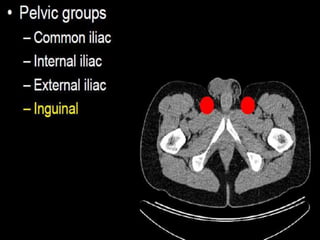

CT cross sectional anatomy.